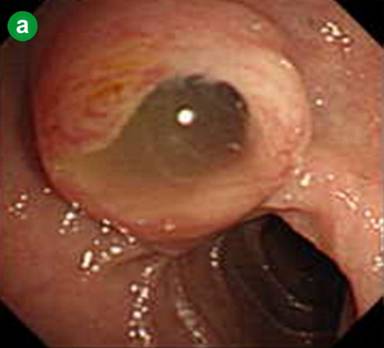

A 75-year-old man was admitted to the hospital because of acute onset of severe epigastric pain and body weight loss. On physical examination, palpable mass and tenderness of upper abdomen was noted. Laboratory studies revealed elevated C-reactive protein (7.0 mg/dL; reference range: 0-0.5 mg/dL), CEA (39.7 ng/mL; reference range: 0-5 ng/mL), CA 19-9 (62.3 U/mL; reference range: 0-37 U/mL) and HbA1c (13.2%; reference range: 3.4-5.8%). Results of complete blood count, plasma levels of electrolytes, tests of coagulation, amylase, lipase, kidney and liver function were within normal limits. Computed tomography (CT) and magnetic resonance imaging (MRI) of the abdomen showed a markedly dilated main pancreatic duct (45 mm), a papillary tumor (20 mm in diameter) protruding into the main pancreatic duct of the distal pancreas and splenic vein obstruction (Figure 1abc). On duodenoscopy with a lateral viewing of endoscope, mucus was discharged from the enlarged papilla of Vater (Figure 2a). Peroral pancreatoscopy was performed, revealing the papillary tumor on the main pancreatic duct (Figure 2b). Pathological examination of biopsy specimens of the tumor showed papillary mucinous adenoma (Figure 2c).

Figure 2. a Duodenoscopy with a lateral viewing of endoscope showed mucus discharged from the enlarged papilla of Vater. b. Peroral pancreatoscopy showed the papillary tumor on the main pancreatic duct. c. Pathological examination of biopsy specimens of the tumor showed papillary mucinous adenoma. |